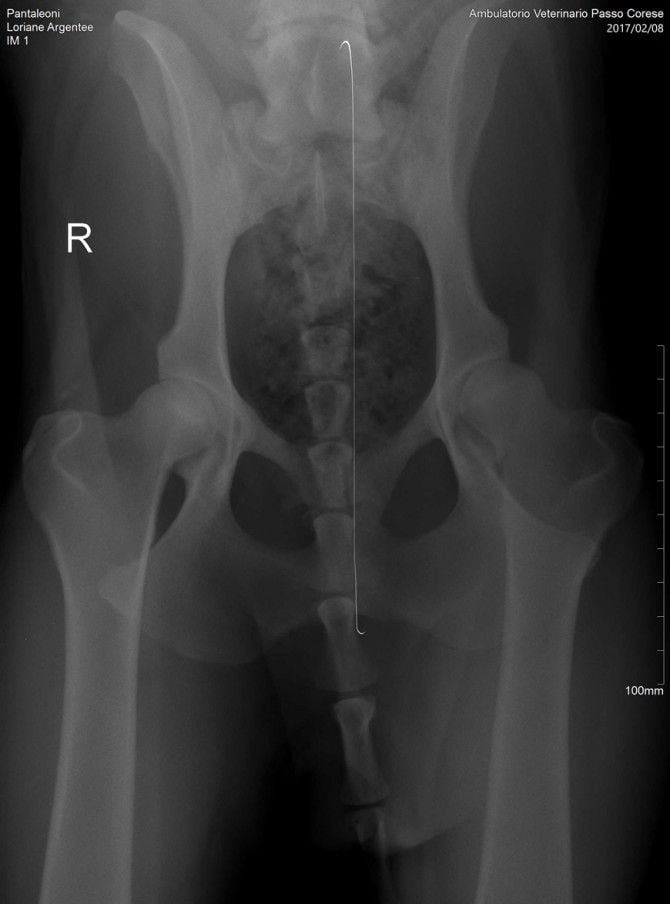

Loriane argentee Des Gardiens De Rome

femelle

Berger de Beauce

née le

28/09/2015

LORIANE Argentée des Gardiens de Rome

Informations sur Loriane argentee Des Gardiens De Rome

| Sexe | Femelle |

| Couleur | Arlequin |

| Puce | 380260002539580 |

| Inscrit au LOF ? | Italie |

| N° origine | LO15184318 |

| Statut | Retraité |